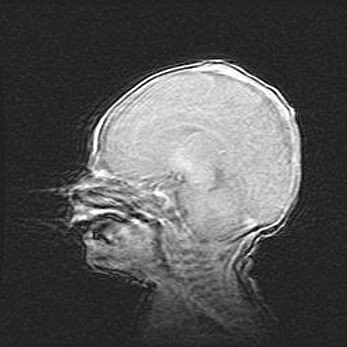

Наружная гидроцефалия с возможной атрофией височных областей.

Возраст: 28 дней

Вес: 3670 г

Пол: мужской

Окружность головы: 38 см

Срок гестации: 40 недель

Гидроцефалия головного мозга у новорожденных – это заболевание, которое характеризуется скоплением избыточного количества спинномозговой жидкости в желудочковой системе головного мозга в результате затруднения её перемещения от места выработки к месту поглощения в кровеносную систему или вследствие нарушения абсорбции. При открытой наружной форме гидроцефалии у новорожденных расширяются и переполняются субарахноидные пространства.

При нормотензивных  формах,  которые,  как  правило,  являются  следствием  перенесенных ишемических  повреждений  паренхимы  мозга,  возможно  сочетание микроцефалии  с нормотензивной гидроцефалией. В основе данных изменений лежит атрофия больших полушарий с преимущественной  локализацией  в  лобно-височных  областях.